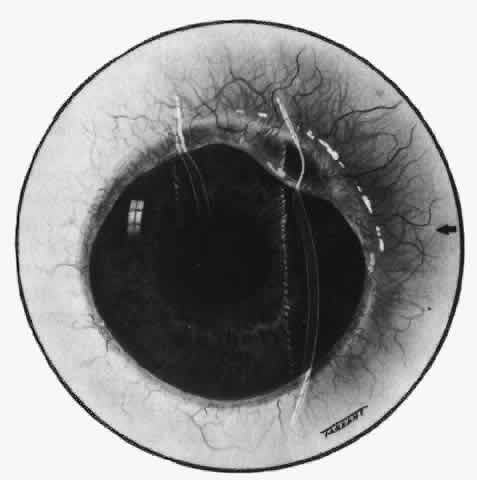

With the increasing use of anterior segment fluorescein angiography in the early detection of severe necrotizing disease of the sclera, it is necessary to have an understanding of the normal anatomy of the vasculature of the anterior segment of the eye.3–5 The blood supply to this region is enormous, being derived from the anterior ciliary arteries, but with extensive collateral arterial anastomoses to the posterior ciliary arteries at the root of the iris (Fig. 1). The anterior system is readily visible with the slit lamp and by anterior segment fluorescein angiography, especially if the eye is inflamed, and its recognition is of vital importance in the differentiation of episcleral and scleral conditions. The separation and displacement of these vascular layers give the most important clinical clues to the site and, hence, the severity of the inflammation. On slit lamp examination, three layers of vessels are readily visible. The conjunctival plexus, which is the most superficial layer of vessels, can be moved over the underlying structures. The superficial episcleral capillary plexus (Fig. 2) is a radially arranged series of vessels lying within the parietal layer of Tenon's capsule. The vessels in this layer anastomose at the limbus with the conjunctival vessels, with other members of the same plexus, and with the deep plexus. The deep episcleral capillary network (see Fig. 2) is closely applied to the sclera in the visceral layer of Tenon's capsule. The vessels anastomose freely with each other, forming a syncytium. The large vessels to and from the intrascleral plexus traverse the episclera near the insertions of the muscles. The conjunctival and superficial episcleral vessels can be blanched with 1:1000 epinephrine or 10% phenylephrine, but the deep vessels are affected slightly. This is of considerable assistance when attempting to differentiate deep and superficial inflammation.

Fig. 1. Anterior view montage of a cynomolgus monkey ocular casting with Tenon's and episcleral vessels removed. The anterior ciliary arteries (ACA) arborize at the limbus and interconnect via their lateral branches to form the episcleral circle. (CM, ciliary muscle capillary bed; CV, choroidal veins; EC, episcleral circle. (Original magnification, X20). (Morrison JC, van Buskirk EM: Anterior collateral circulation in the primate eye. Ophthalmology 90:707, 1983)

Fig. 2. The normal relationships of the capillary networks that can be seen with the slit lamp are a conjunctival (easily mobile) network, a superficial episcleral network in the parietal layer of Tenon's capsule, and a deep episcleral plexus closely applied to the sclera. These relationships are much more obvious in inflamed eyes (see Figs. 13, 14, and 30). (Watson PG, Hayreh S, Awdry P: Episcleritis and scleritis. Br J Ophthalmol 52(3):278– 279, 1968)